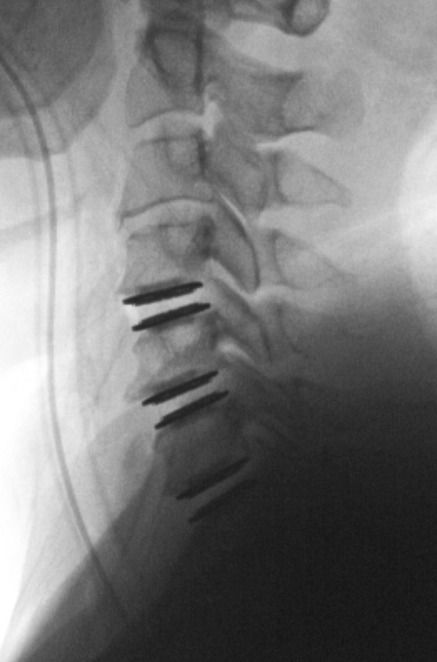

أعلن مستشفى "ذا فيو" عن زيارة الجراح العالمي الدكتور أليكساندر راسولي المختص بجراحة العمود الفقري والقادم من بيفيرلي هيلز، كاليفورنيا - الولايات المتحدة الأمريكية وقيامه بعملية استبدال القرص الاصطناعي للعمود الفقري للرقبة على ثالثة مستويات. تم إجراء العملية المعقدة في مدة 90 دقيقة فقط من قبل الدكتور ألكساندر راسولي، وهو مختص بطب العمود الفقري الجراحي وغير الجراحي وحاصل على البورد الأميريكي وهو مختص في العلاج الجراحي وغير الجراحي لاضطرابات العنق والصدر والعجز العمودي للعمود الفقري، والاضطرابات التنكسية، وإصابات العمود الفقري، وتشوهات الكبار والأطفال بما في ذلك اعوجاج العمود الفقري، وأورام العمود الفقري، والجراحة القليلة التدخل. اكتسب الدكتور راسولي شهرة في مجال اضطرابات العمود الفقري بعد اكتشافه في عام 2007 لطريقة جديدة لإعادة توليد الخلايا العصبية التالفة بسبب إصابات الحبل الشوكي باستخدام زراعة الأعصاب المحيطية.

تمكنت المريضة التي أجريت لها العملية بنجاح فائق من المشي بدون أي آلام وكانت جاهزة للخروج من المستشفى في ذات اليوم ويتم حاليًا متابعة حالتها الصحية من قبل الفريق المختص.

في تعليقه عن زيارته لمستشفى ذا فيوس ، قال الدكتور ألكساندر راسولي: زلقد سعدت بالقدوم إلى مستشفى زذا فيوس في الدوحة - قطر، لاجراء أول عملية في المنطقة لاستبدال القرص الاصطناعي للفقرات العنقية على ثالثة مستويات. لم يكن بالامكان إجراء العملية دون الكادر المميز والتكنولوجيا الطبية المتطورة الموجودة في مستشفى زذا فيوس، وأعتقد أن هذا المستشفى سيكون الصرح الطبي الأول في مجال الرعاية الصحية في الشرق الأوسط.